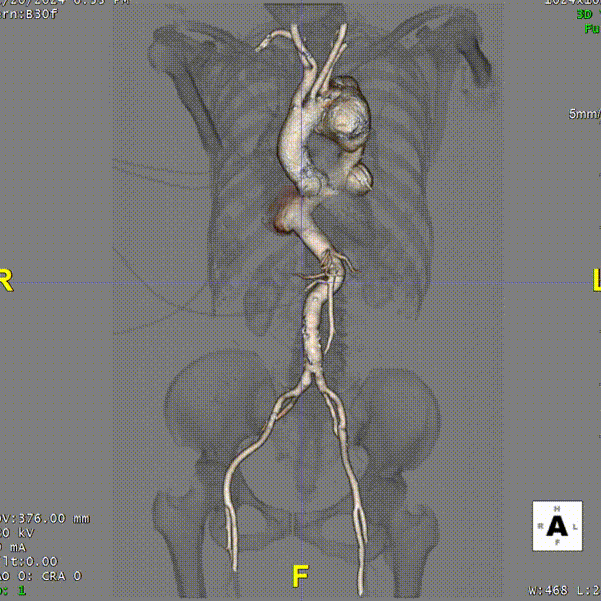

术前CTA详解

术前CTA.

术前3D重建

巨大胸主动脉瘤,直径70mm

病变累及LCCA附近,小弯侧锚定区长度11mm,非常极限

降主动脉瘤远端锚定区长度

INA后缘至CA上缘长度